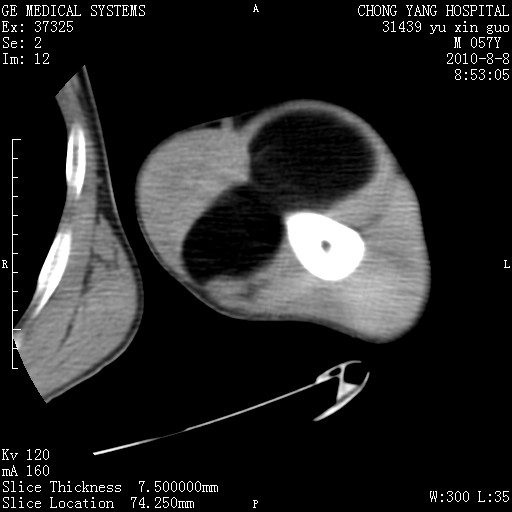

标题: CT28267:M57Y 上臂包块8年余。 [打印本页]

标题: CT28267:M57Y 上臂包块8年余。

上臂软组织内脂肪瘤。

软组织内脂肪瘤

包膜光滑、完整的脂肪密度肿块,支持脂肪瘤。